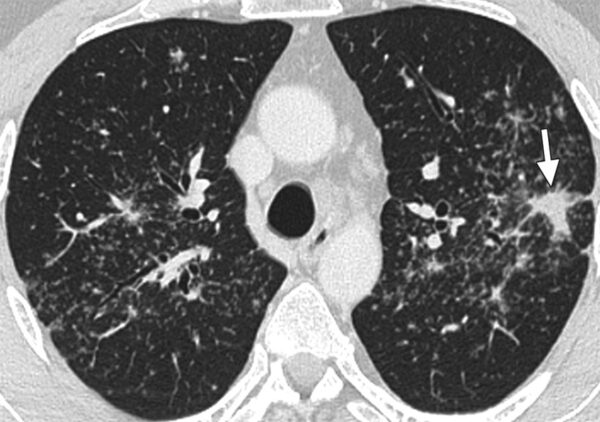

- Etapa III: Afectación parenquimatosa aislada En esta fase, la linfadenopatía hilar puede no ser tan prominente o puede haber disminuido, y el hallazgo radiográfico principal es la afectación del parénquima pulmonar por sí sola. Esto se manifiesta como infiltrados pulmonares difusos que pueden tener una apariencia reticular (red de líneas finas en las imágenes) o nodular. La afectación parenquimatosa sin la presencia significativa de linfadenopatía hilar sugiere un avance en la enfermedad, con posibles síntomas como tos, dificultad para respirar y malestar en el pecho.

Manifestaciones parenquimatosas:

- Infiltrados reticulares difusos: Este patrón en las radiografías se presenta como una red de líneas finas que reflejan la infiltración del tejido pulmonar por células inflamatorias.

- Infiltrados focales, sombras acinares, y nódulos: A veces, los infiltrados pueden ser focales o presentar una apariencia más específica en forma de sombras acinares (pequeñas áreas de opacidad en el pulmón) o nódulos.